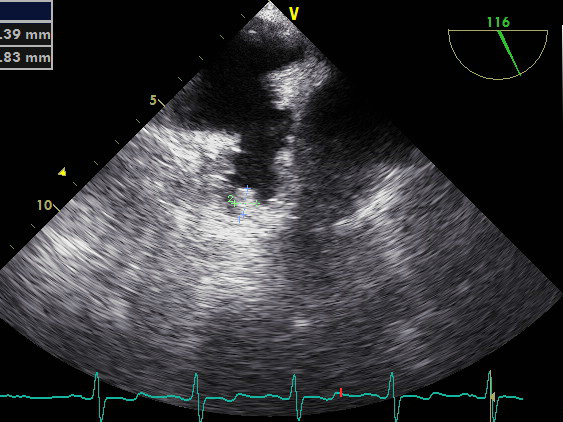

图1:2020年6月TEE多角度显示心耳尖部局部血栓